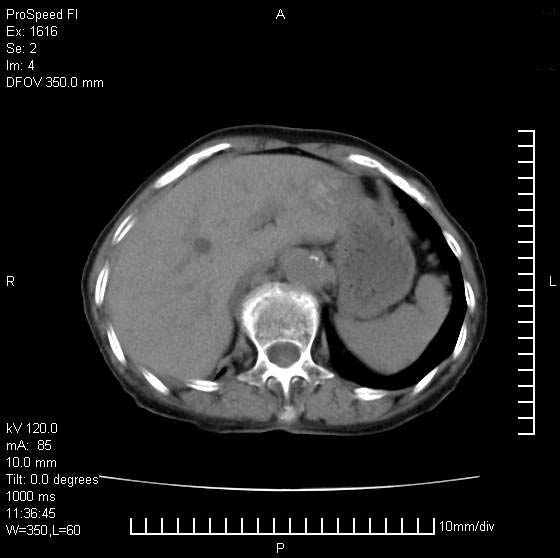

患者无明显临床症状,肝左叶发现一个圆形密度不均的低密度灶,边界较清楚,大小37x45mm,ct值35-70,患者犹豫做增强,如有增强片,我再发上,现先请各位老师会诊.

左肝外叶可见较大圆形低密度影,病灶可见较光整清晰边界,病灶内可见多量条状稍高密度影,右肝前叶亦可见圆形结节状低密度影,边界清晰,密度均匀,考虑1肝多发囊肿,左肝囊肿内出血2肝包虫病3左巨块型肝癌出血合并右肝转移或合并右肝囊肿

病灶内高密度影,从ct值上看是血的密度还是某种纤维组织呢?似乎有内缘有包膜,肝脏各叶比例略失调,脾脏有点大.

hcc(巨块型)伴出血,突破肝包膜,肝胃韧带内,腹主动脉旁淋巴结转移;肝硬化

肝左叶不均匀占位,内有斑片状高密度出血灶,内侧缘似有假包膜,腹主动脉周围及肝门区结构紊乱,似有增大淋巴结,考虑:肝左叶hcc并淋巴结转移。建议增强扫描除外其他。